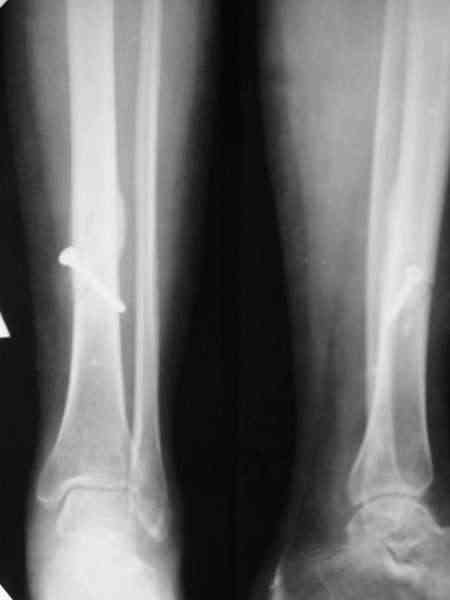

Типичный косо-спиральный перелом голени с низкой энергией, большеберцовая внизу, а сверху малоберцовая, и применение интрафрагментарного компрессионного шурупа можно оправдать, когда для

фиксации перелома выбран метод открытой фиксации пластинами, где пластина после стабилизации и компрессии перелома действует как нейтрализующая сила.

Если винт все-таки стягивающий (компрессирующий), а не "позиционный", то это чистой воды философия АО, так называемый принцип Mini-Max. Философии Илизарова , пожалуй пртиворечит: фиксация не совсем внеочаговая:)